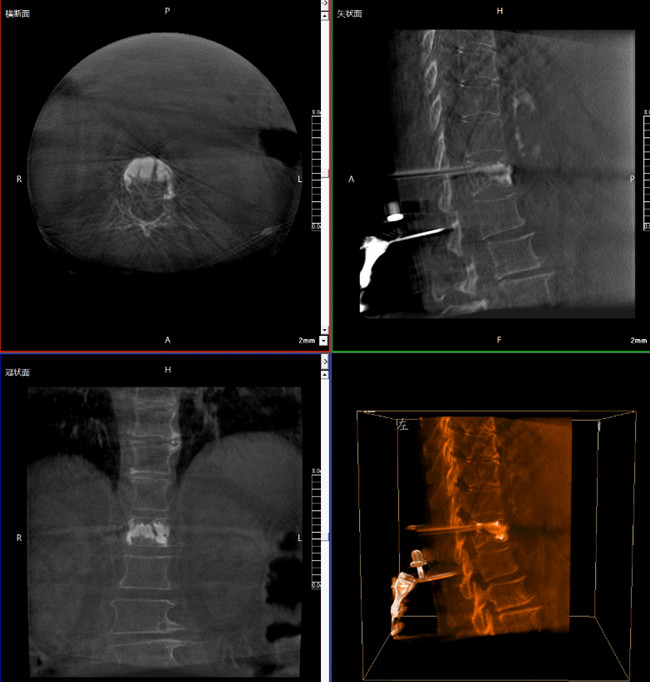

步驟一:C形臂三維重建+機器人手術規劃

使用普愛醫療三維C形臂對患者進行胸椎影像掃描及三維重建,圖像被同步傳輸到普愛醫療骨科機器人導航系統。

借助骨科機器人的規劃軟件進行術前手術路徑模擬規劃,找到穿刺位置和角度,操作機械臂快速完成手術入點的準確定位。

*骨水泥置入效果良好